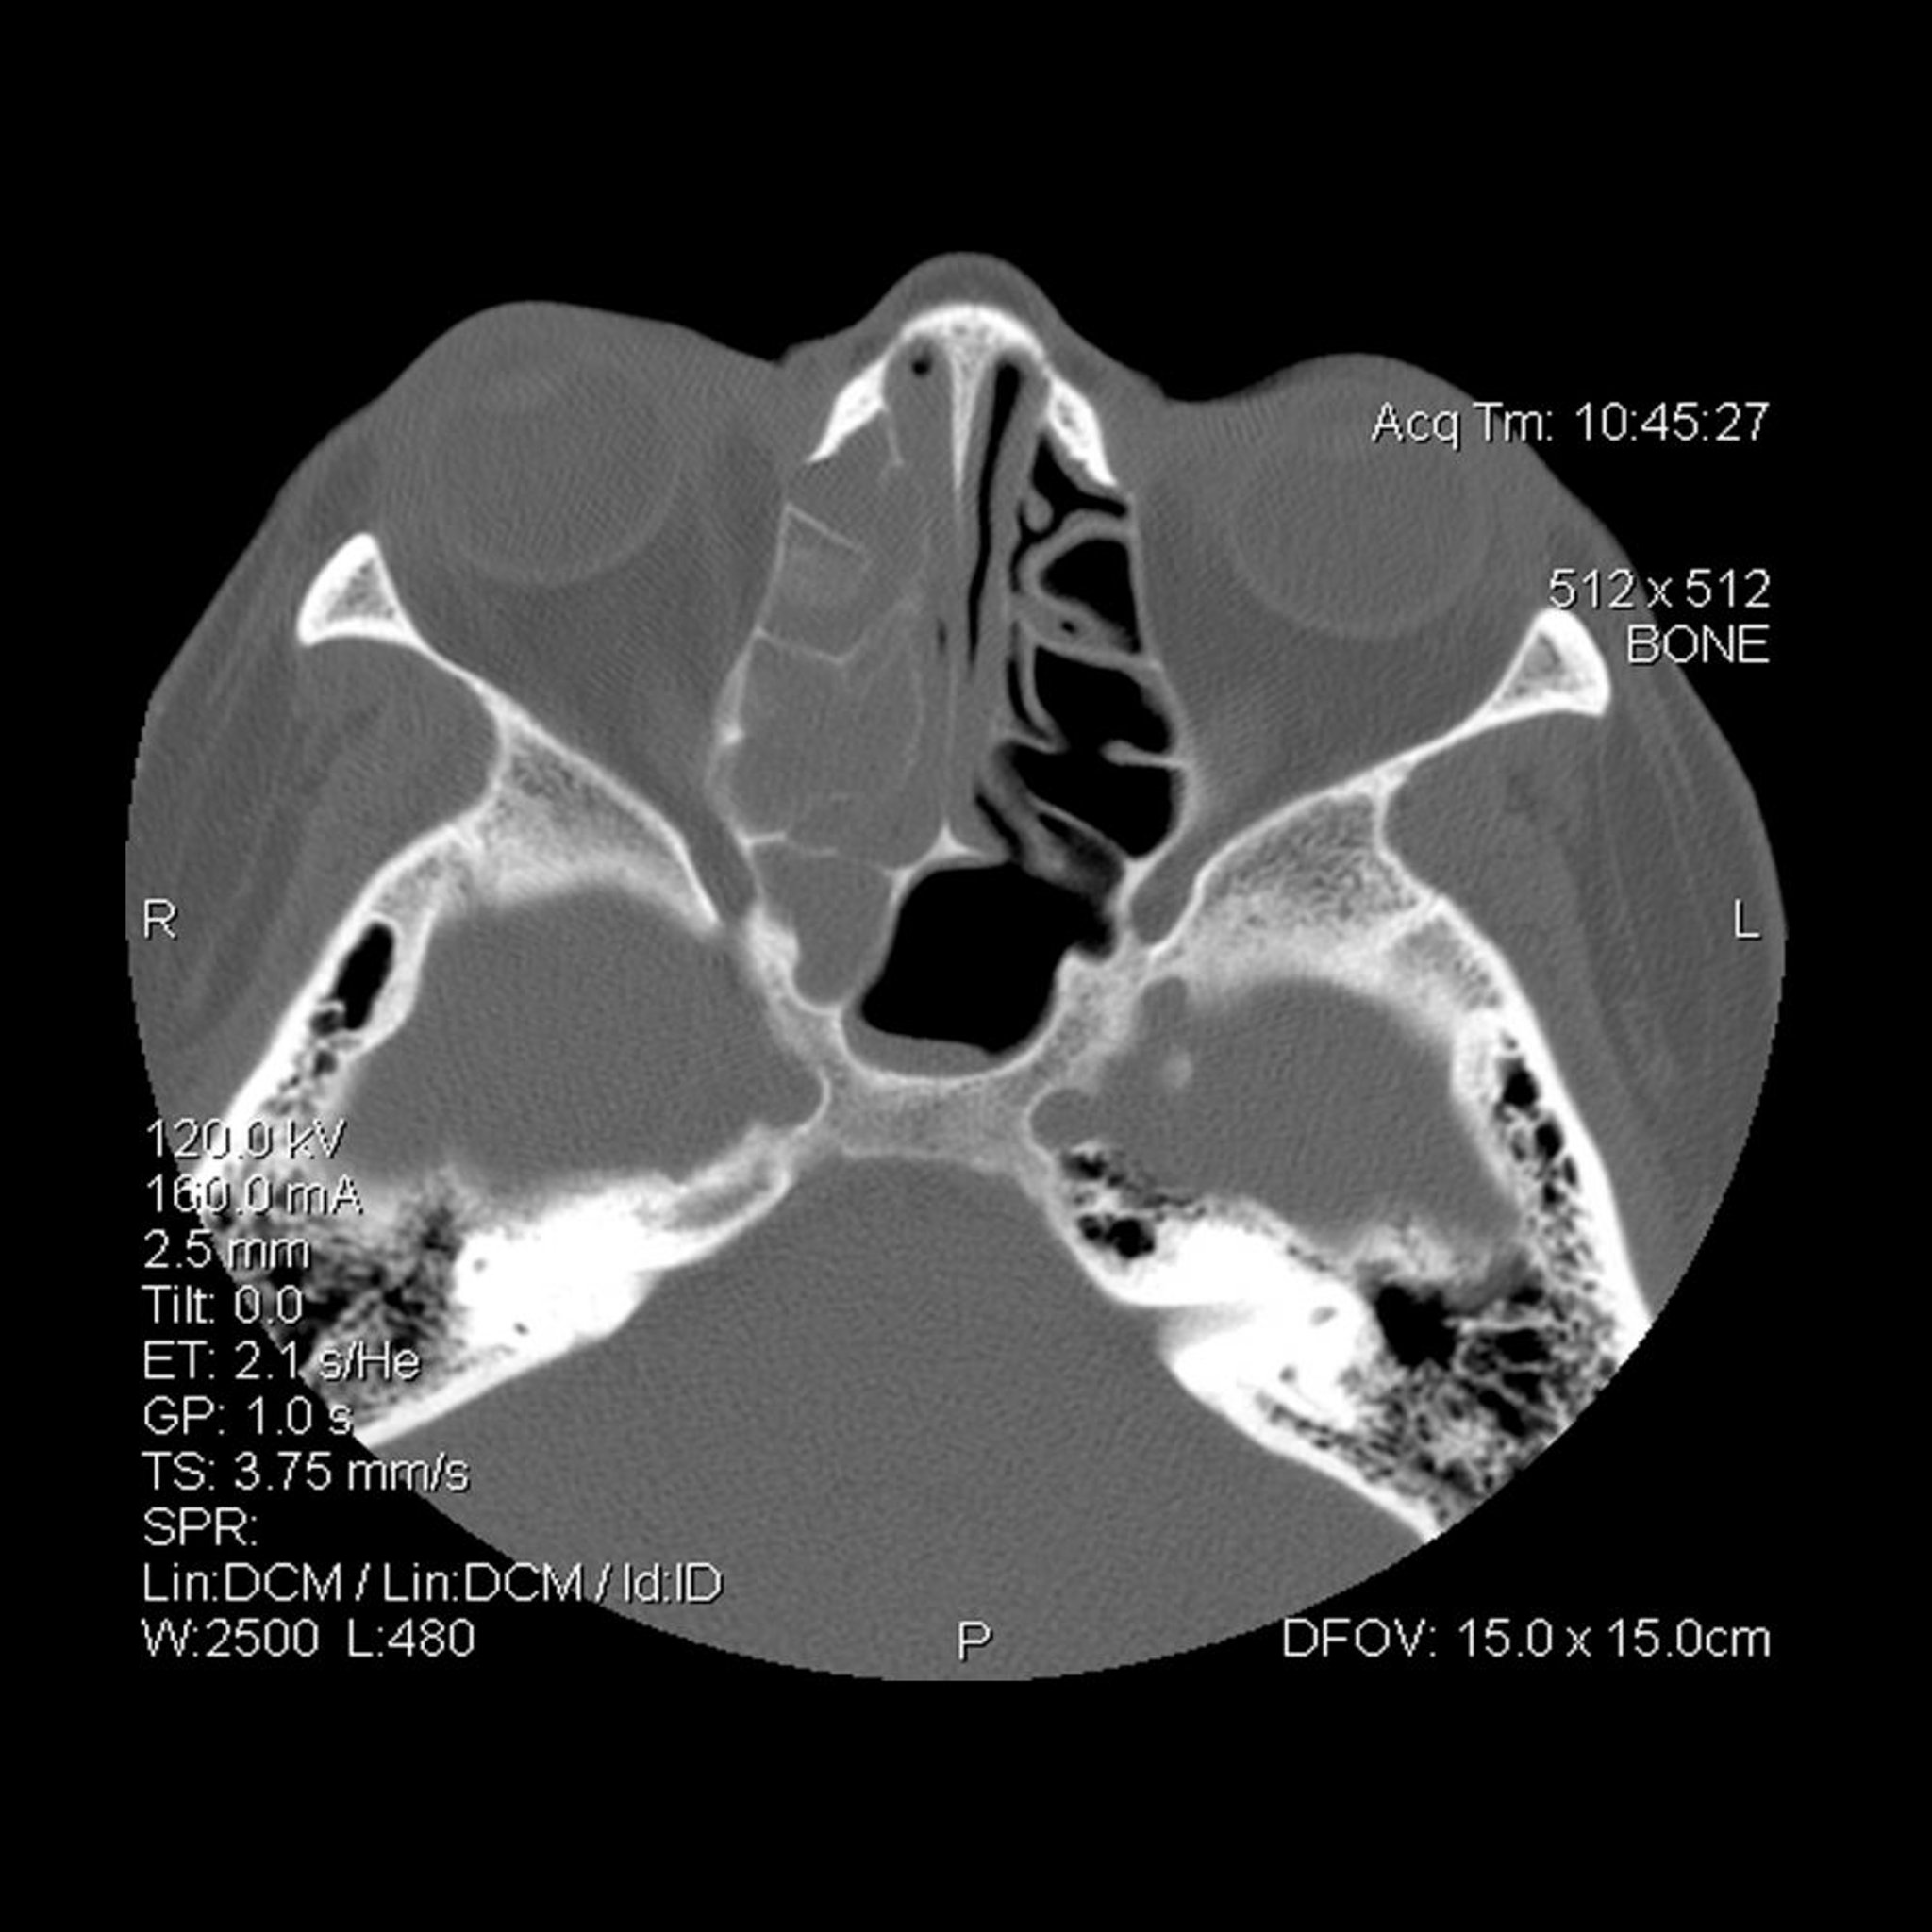

Opacificación de los senos etmoidales y esfenoidales derechos (a la izquierda del lector).